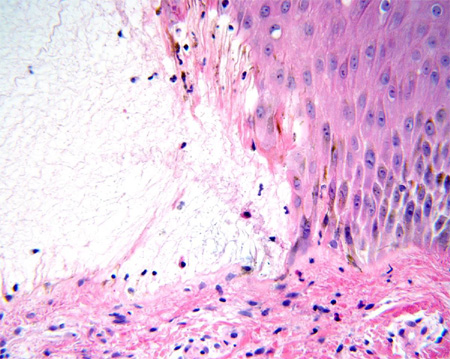

[Figure caption and citation for the preceding image starts]: В полости пузыря имеется сеть фибрина, в то время как дермальный инфильтрат содержит большое количество эозинофиловИз коллекции д-ра Весны Петрон-Росик (Dr Vesna Petronic-Rosic) [Citation ends].

[Figure caption and citation for the preceding image starts]: В полости пузыря имеются фибрин и эозинофилыИз коллекции д-ра Весны Петрон-Росик (Dr Vesna Petronic-Rosic) [Citation ends].